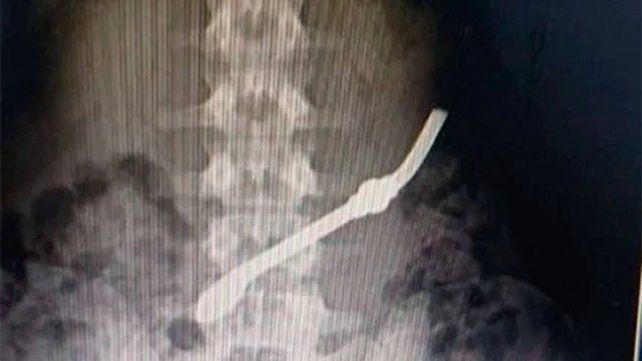

Un interno de la Unidad Penal 7 de Gualeguay se tragó una bombilla metálica como medida de protesta tras una disputa familiar. Como consecuencia del hecho, el hombre debió ser trasladado de urgencia al Hospital San Antonio.

El detenido tuvo que ser intervenido en el hospital San Antonio. Quedó bajó custodia. Trascendió que quiso llamar la atención de su pareja.

El hecho ocurrió cuando el hombre, enojado porque su pareja no había acudido a visitarlo, decidió autoflagelarse ingiriendo el objeto. La gravedad de la situación obligó a su rápido traslado al centro de salud, donde recibió atención médica para evitar complicaciones mayores.